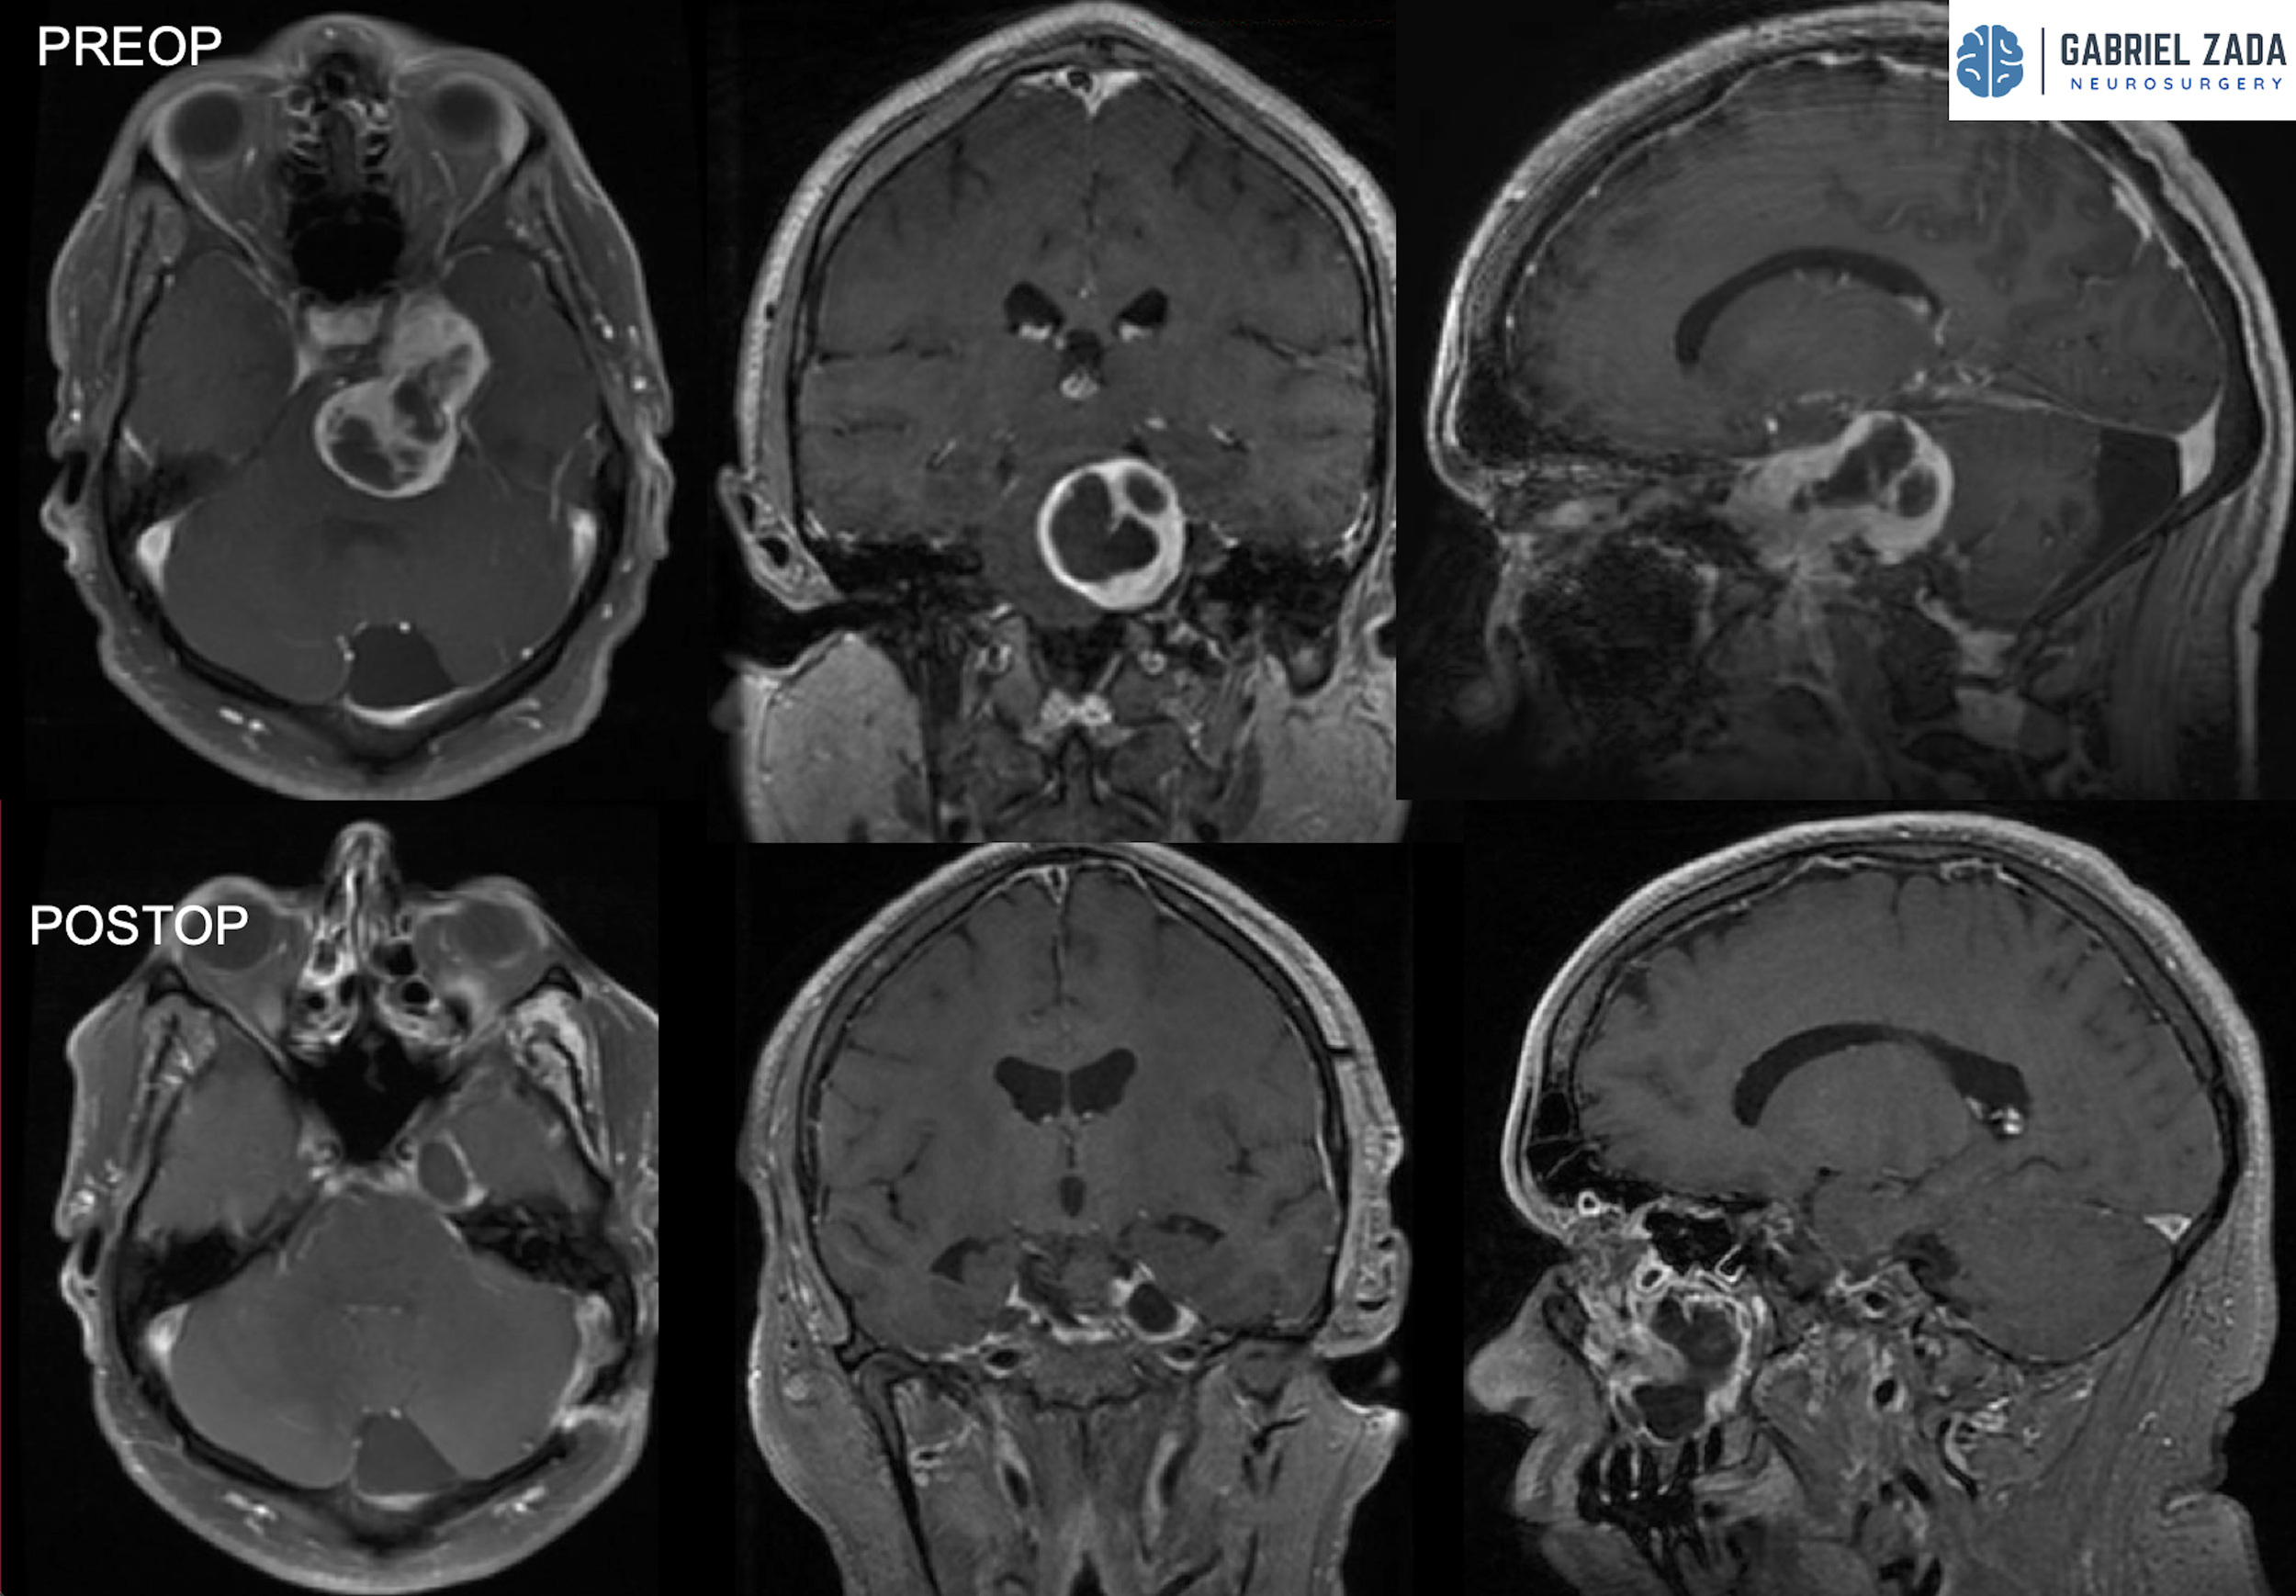

Explore this comprehensive gallery featuring pre‑ and post‑operative imaging of patients with skull‑base tumors treated by Gabriel Zada, MD, MS, FAANS, FACS. These cases highlight Dr. Zada’s expertise in advanced neurosurgical techniques and outcomes.

*Representative cases shown for educational purposes. All images de-identified. Individual results vary.